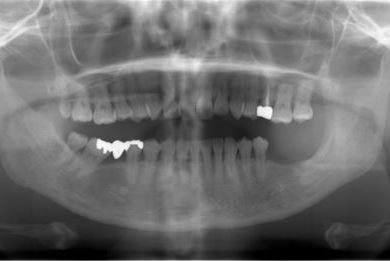

| 性別/年齢 | 女性 / 46歳 | ||||||||||||||||||||||||||||||||

| 主訴 | 左奥歯のインプラント治療を希望。 | ||||||||||||||||||||||||||||||||

| 治療方針 | 左下奥、欠損部分をインプラント治療にて、機能的・審美的回復を行う。 | ||||||||||||||||||||||||||||||||

| 治療内容 | インプラント2本、ハイブリッドセラミッククラウン2本 | ||||||||||||||||||||||||||||||||

| 総治療費 | 399,000円 | ||||||||||||||||||||||||||||||||

| 治療期間 | 5ヶ月 |